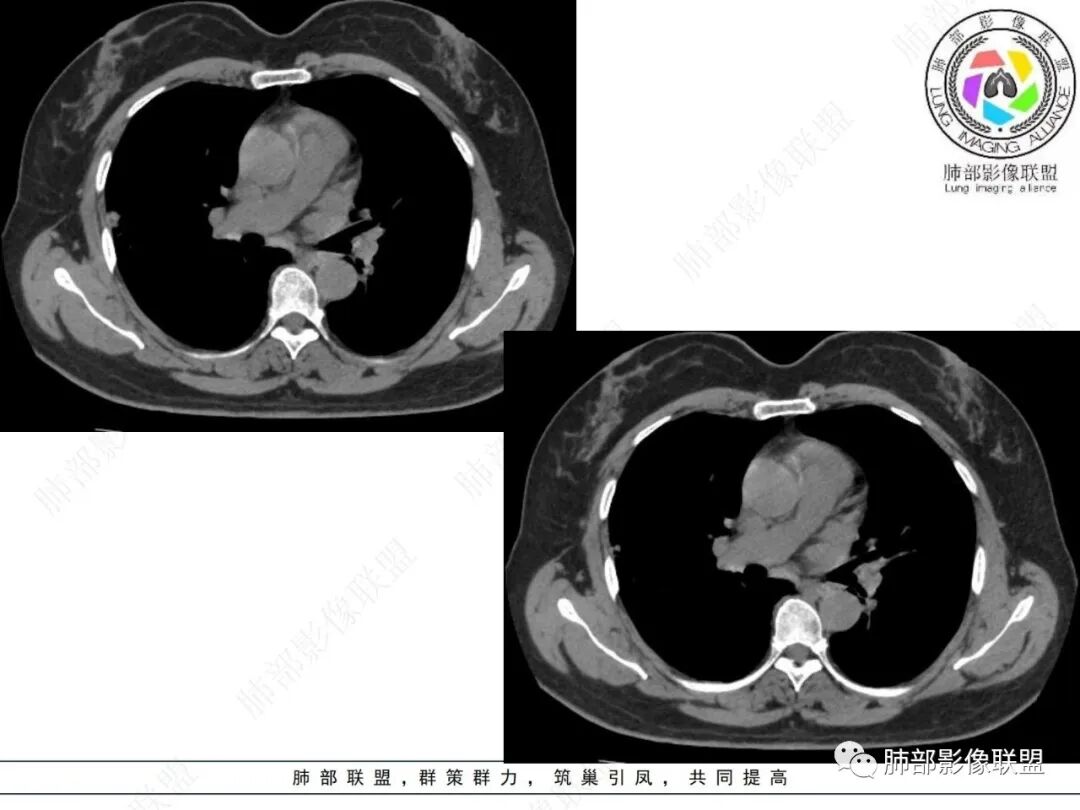

2.影像特点:

右肺上叶胸膜下混合磨玻璃团片影。

周围磨玻璃部分间杂条索状高密度区,密度欠均匀(可疑重力分布趋势),其磨玻璃影边界大多较清楚或可分辨,部分“L型”边缘,提示小叶间隔阻挡可能。血管穿行自如,可疑远端支气管进入。

实性部分较密实,不规则,隐约见棘突或刺状突起,未见钙化、空洞或液化区,实性边缘可见斑状略低密度间隙(借用王兆宇老师课件,称其呈“松软”的形态)。动脉期实性部分较明显不均匀强化,如果有完整增强图,还可以观察内部血管情况。

纵隔窗相对肺窗病灶相对小,仅部分实性影呈现。病灶张力不高,相邻胸膜增厚(糊墙),未见明显胸膜牵拉凹陷。

未见卫星病灶,远处未见磨玻璃结节影。

双肺门及纵隔未见明显增大淋巴结。心包及胸腔未见积液。